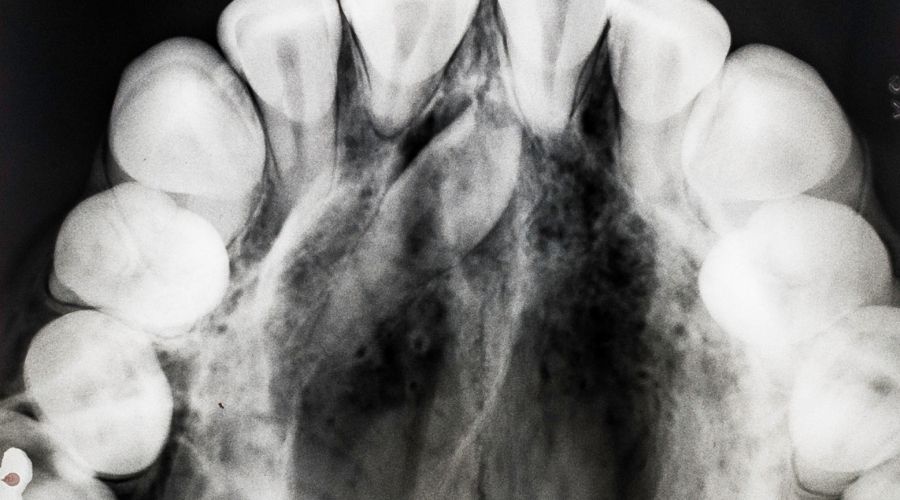

En muchos casos pasa desapercibido, oculto bajo la encía, y solo se revela al hacer una radiografía. En otros, erupciona y se deja ver entre los dientes delanteros o cerca de los molares.

El diente supernumerario más habitual recibe el nombre de mesiodens, y suele encontrarse entre los incisivos superiores.

O simplemente que el dentista lo descubra en una radiografía panorámica de control.

Por eso insistimos tanto en las revisiones odontopediátricas. En Rubal Dental solemos hacer la primera radiografía panorámica a los seis años, cuando empiezan a salir los primeros dientes permanentes.

Es una prueba rápida, segura (de muy baja radiación) y tremendamente útil para detectar cualquier anomalía antes de que dé problemas.

Una radiografía a tiempo puede evitar muchos dolores de cabeza (y de dientes) más adelante.